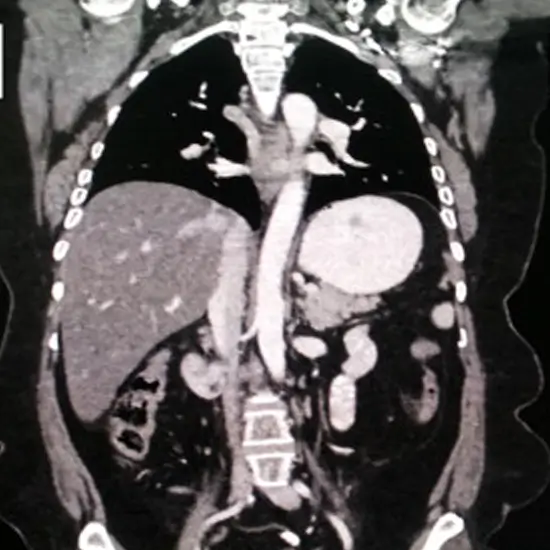

CECT Chest & Upper Abdomen - Test, Cost & Procedure

CECT Chest Upper Abdomen

CECT Chest & Upper Abdomen is a contrast study of the chest and abdomen in which dye is injected to examine the internal structure of chest and abdomen pathology.

In this scan, you may need to drink oral contrast for 2 hours before the exam. After that, contrast is injected into the patient's body, and images are taken in arrested inspiration.